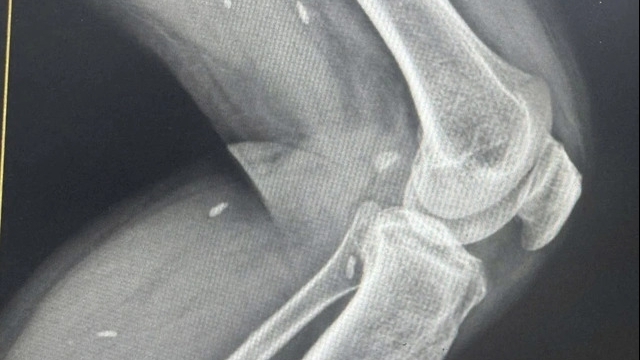

Bệnh nhân nữ Nguyễn Thị M (98 tuổi), xã Đồng Ích, huyện Lập Thạch, tiền sử có u xơ tử cung. Bà M vào viện trong tình trạng đau tức hạ vị kèm theo rối loạn đại tiểu tiện.

Tại đây, bệnh nhân Nguyễn Thị M được khám và chẩn đoán u xơ tử cung biến chứng chèn ép trực tràng và bàng quang.

Kết quả cuộc phẫu thuật đã được tiến hành thành công, bóc khối u xơ (11cm) cắm sâu về phía trực tràng, u xơ có 1 phần đã thoái hóa và cắt tử cung bán phần, tình trạng hậu phẫu bệnh nhân ổn định.